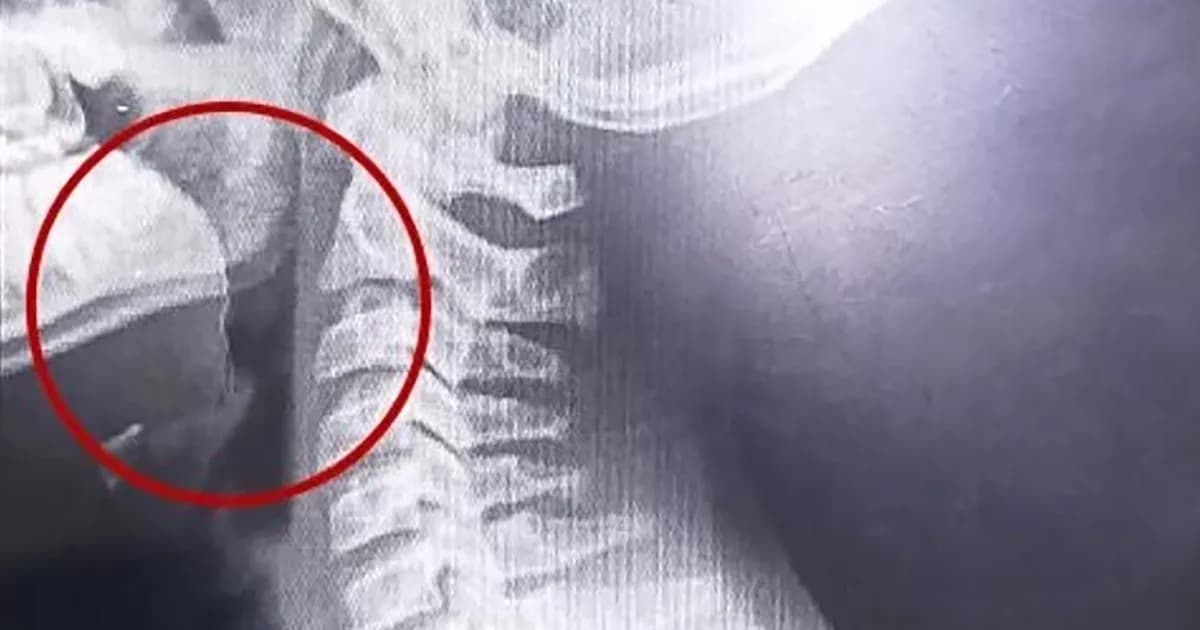

Al llegar al hospital, el equipo médico actuó rápidamente y comenzó con una evaluación exhaustiva del estado del joven. Los profesionales encontraron lesiones en la garganta y decidieron internarlo de inmediato para realizar más estudios. Se llevaron a cabo diversas pruebas para descartar infecciones o la presencia de bacterias, cuyos resultados fueron negativos. Sin embargo, la respuesta a la causa del problema llegó a través de estudios por imágenes, que revelaron un objeto extraño en la vía aérea superior del adolescente.

El parte médico indicaba que el paciente ingresó "clínica y hemodinámicamente estable, afebril, vigil, reactivo, normohidratado y normoperfundido". Luego de una consulta con el servicio de otorrinolaringología, se determinó que el joven necesitaba una intervención quirúrgica urgente. En quirófano, el equipo médico logró localizar un alambre fino que estaba incrustado en su garganta, una situación que había pasado desapercibida en las evaluaciones previas.

La intervención, realizada mediante laringoscopía, se llevó a cabo sin inconvenientes. Tras una evolución favorable, el adolescente fue dado de alta y pudo regresar a su hogar, dejando atrás un episodio que pudo haber tenido consecuencias mucho más graves. Este caso resalta la importancia de una atención médica adecuada y oportuna ante situaciones de emergencia, así como la necesidad de estar alerta ante síntomas inusuales en la salud de los más jóvenes. La comunidad, conmovida por el suceso, reflexiona sobre la importancia de la prevención y la atención médica en situaciones críticas, con la esperanza de que no se repitan incidentes de esta naturaleza en el futuro.